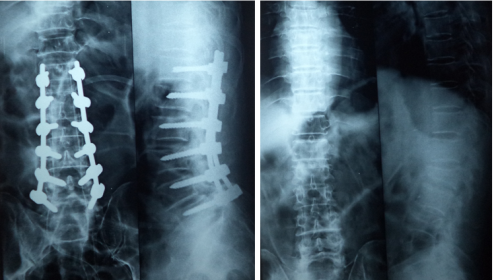

➤ Spinal injuries and management Arthroscopy

The vertebral column and the vertebrae give shape to the body. They give the height to the body and maintain the erect position. They help us to bend forwards, to turn to sides and to bend backwards. This vertebral column gives protection to the spinal cord and nerves which travel from the base of the brain to the tip of the vertebral column. Vertebral fractures occur due to the fall from height. They can be injured during the time of accidents.